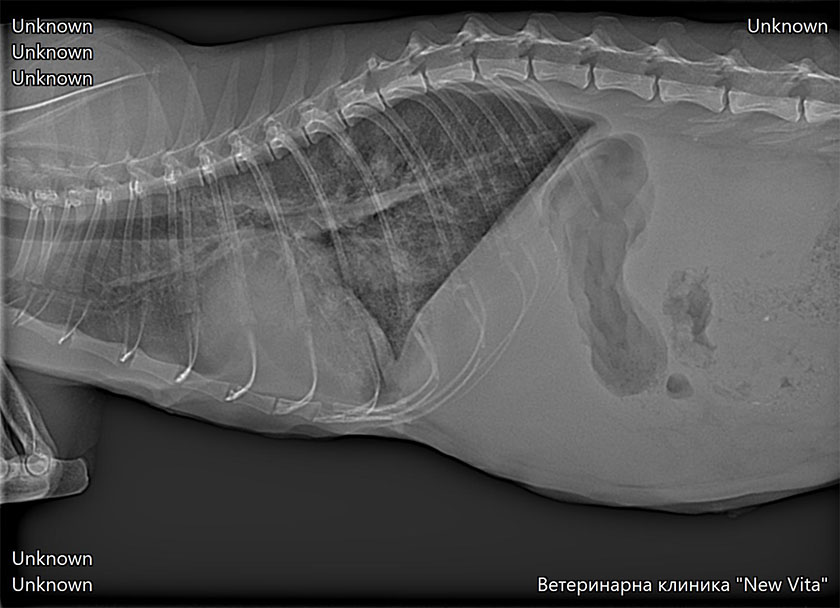

Най-честата рентгенологична находка при котки със сърдечни проблеми е наличието на плеврален излив, оток на белия дроб, Увеличени белодробни съдове, увеличен сърдечен силует-кардиомегалия (не е задължително да се установи, за да бъде поставена диагнозата, много често сърцето е външни размери). Процедурата по получаване на качествени и диагностични рентгенологични снимки може да бъде отложена докато пациента не бъде стабилизиран. Изискват се минимум две рентгенови снимки в две проекции.

Това са рентгенови снимки на наши пациенти. Те показват наличие на плеврален излив и оток на белия дроб.